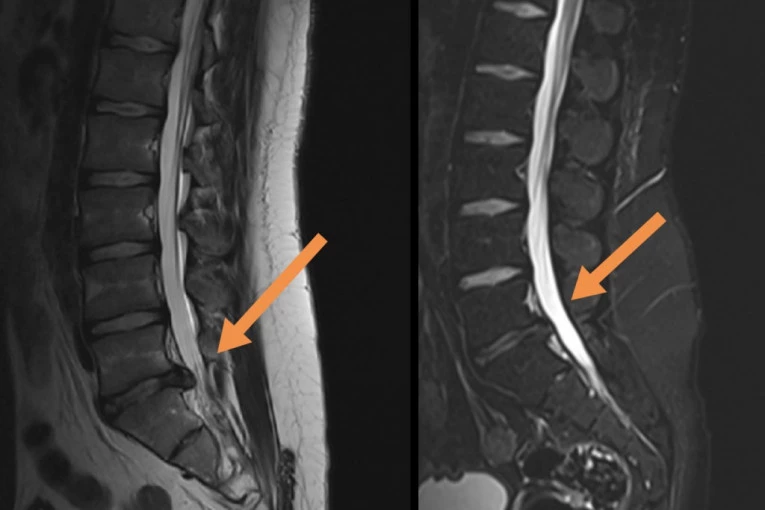

Foto: Promo fotoNajčešći problem bolnih ledja je diskus hernija koja se obično javlja između 30 i 50 godine života. Razlog za ovo jeste što prirodni proces starenja kičmenih diskova počinje već u detinjstvu i ranoj mladosti, tako da nije neobično da bolest nastane i kod osobe od dvadesetak godina. Simptomi zavise od nivoa u kom se javio problem. Najčešće se javlja u nivou L5/S1, tada bol ide duž čitave noge sve do stopala, obično je prisutan i bol u listu uz jak spazam mišića, a može doći i do pada stopala, kao i oštećenja sfinktera ( učestalo mokrenje, nemogućnost mokrenja, erektilna disfunkcija). Vrlo cesto se desava da pacijenti lutaju u trazenju dijagnoze, desava se da idu kod urologa, nefrologa, ili gastroenterologa misleći da je problem te prirode. Kad je vrat u pitanju, obično stradaju C4/C5/ i C6. Bol se obično locira u vratu sa ograničenim pokretima, jakim spazmom a vrlo često se desava da bol idu duž ruku uz trnjenje i slabost mišića. Glavobolje i vrtoglavice mogu se javiti kod izraženih degenerativnih promena i suženja vertebralnih arterija koje ishranjuju mozak (glavobolje su obično potiljačne, zujanje u ušima, bol ka slepoočnicama, nagon za povraćanje, hroničan umor, pospanost ili nekada čak bol u grudima).

Foto: Promo fotoDekompresijski tretman kičme ili DTK je jedini neoperativni tretman, kompjuterski kontrolisan i dijagnostički povezan, koji postiže odlične rezultate kod teških slučajeva diskus hernije, degenerativnih promena, artritisa, stenoze spinalnog kanala i pritiska na nervne korenove. Dekompresiona terapija kičme deluje tako da putem cikličnih faza distrakcije i relaksacije i pravilnom pozicioniranjem diska dovodi do povećanja međupršljenskog prostora za nekoliko milimetara (1-2), oslobađa živce - između njih, smanjuje bol, trnjenje, glavobolje, vrtoglavice, kao i slabosti u šakama i stopalima. Ovaj tretman stvara negativan pritisak i efekat vakuma u samom diskusu koji se nalazi izmedju dva pršljena i na taj način povlači herniju unutar diska. Vakum povećava cirkulaciju oko diska i tako leči upalni proces. Dekompresijski tretman vrši istezanje receptora u mišićima i ligamentima oko kičmenog stuba, smanjuje pritisak na medjupršljenske zglobove povećavajući pokretljivost kičme. Zatim odvaja, odnosno vrši separaciju pršljenova i povećava prostor izmedju njih, proširenje intravertebralnog foramena i ispravljanje krivina kičmenog stuba. Klinički je dokazana efikasnost ove primene od 85 odsto.